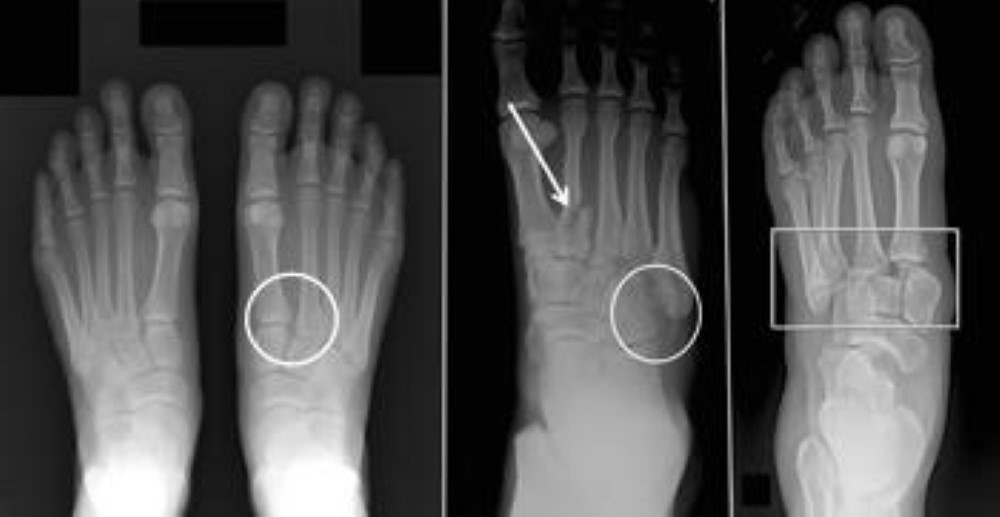

2nd metatarsal is held in mortice created by the three cuneiform bones. Whilst multiple complex classification systems exist. Like all fractures the treatments youll need and your recovery time will depend on the severity of your original injury.

These do little to aid and direct the clinical management of patients. Lisfranc ligament attaches 2nd metatarsal to medial cuneiform. A Lisfranc fracture is a type of broken foot.

Dorsalis pedis may be injured in severe dislocation. In the middle region of your foot midfoot a cluster of small bones form an arch. Injury to 2nd metatarsal often results in dislocation of the other MTs.